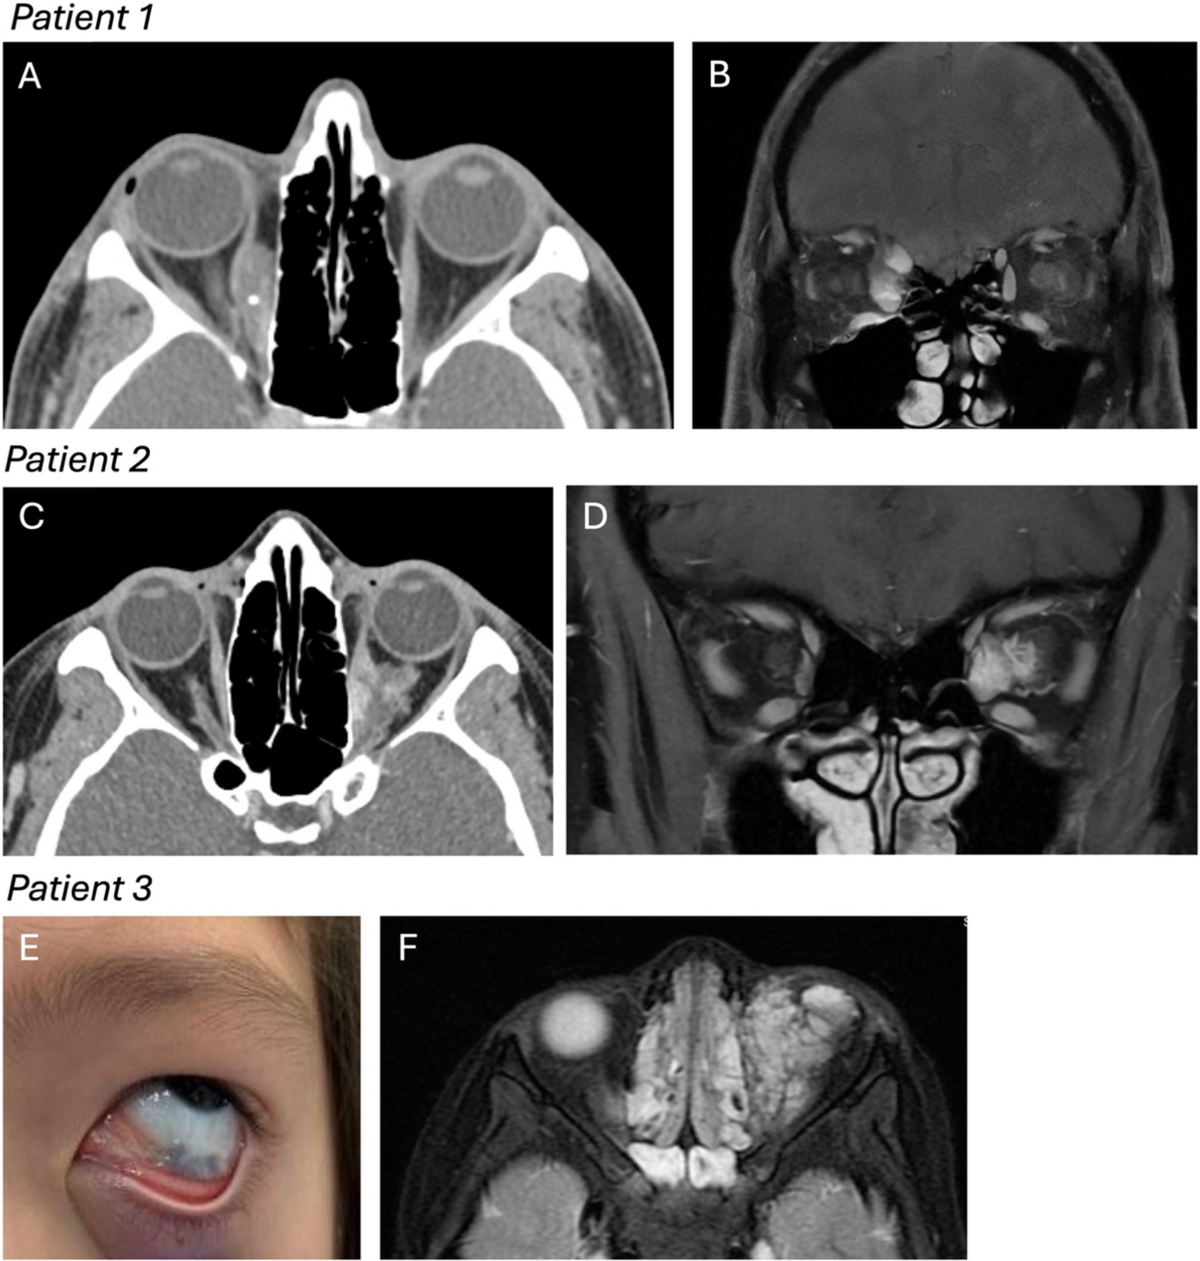

Figure 3 from Orbital Lymphangioma: Characteristics and Treatment Outcomes of 12 Cases | Semantic Scholar

Orbital Lymphangioma in an Adolescent Male: A Case Report and Review of Literature

Bilateral Orbital Lymphangiomas in Two Patients with Generalized Lymphangiomatosis | American Journal of Neuroradiology